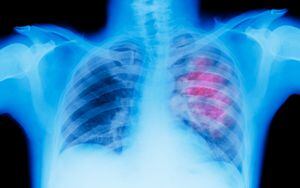

¿Malas noticias?: la quimioterapia puede reactivar el crecimiento de células tumorales “durmientes”; esto explica la ciencia

Grupo de científicos internacionales tiene nuevas pistas sobre por qué reaparece con frecuencia el cáncer de mama.